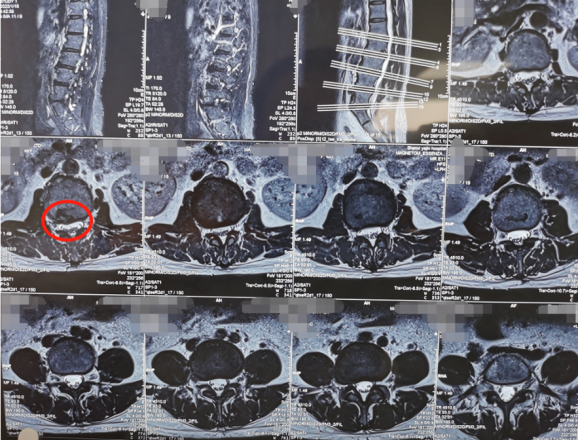

术前影像学资料